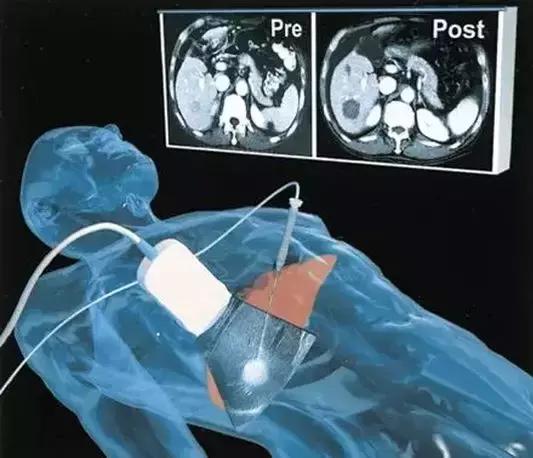

8、微波消融技术

微波微创消融术因具有升温快、组织穿透性强、多点消融可同时进行、消融范围大、可实时监控温度、疗效确切等优点,广泛用于肝癌、肺癌、子宫肌瘤、骨癌、肾癌、胰腺癌、甲状腺肿瘤、脾亢等的治疗,代表着21世纪肿瘤治疗的发展方向。